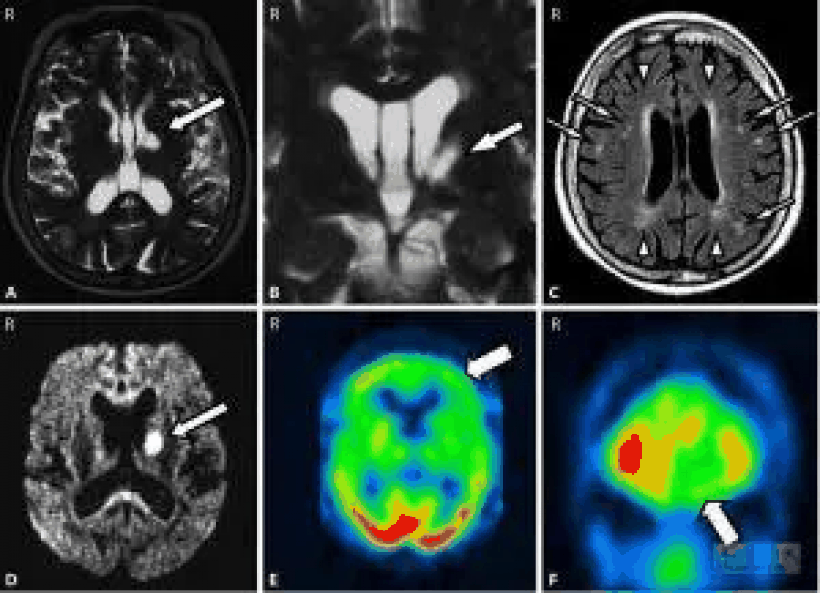

病理生理学

视觉失认症发生在视觉联想皮层或视觉腹侧流的部分受损后,由于其在物体识别中的作用,被称为视觉的什么途径。即使眼睛或引导视觉信息进入大脑的视束没有受损,也会发生这种情况;事实上,当症状无法用这种损害来解释时,就会出现视觉失认症。腹股沟特定区域的损伤可以损害识别某些类别的视觉信息的能力,如视觉失认症的情况。视觉失认症患者一般没有视觉背流(称为视觉通路)的损伤,因为它在确定物体在空间的位置方面起着重要作用,这使得视觉失认症患者能够表现出相对正常的视觉引导行为。